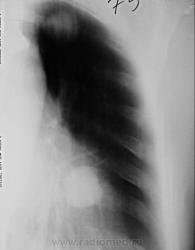

По рентгенографии органов грудной клетки в легких не менее 4 образований... Поскольку живем не в юго-восточной Азии с паразитами, предполагаем в первую очередь метастазы.

1. на фига делали линейную томографию?

Из истории заболевания - оперирована по "женски" чуть больше 1 года назад, получала лучевую терапию....(гинекологи в направлении пишут рак влагалища..